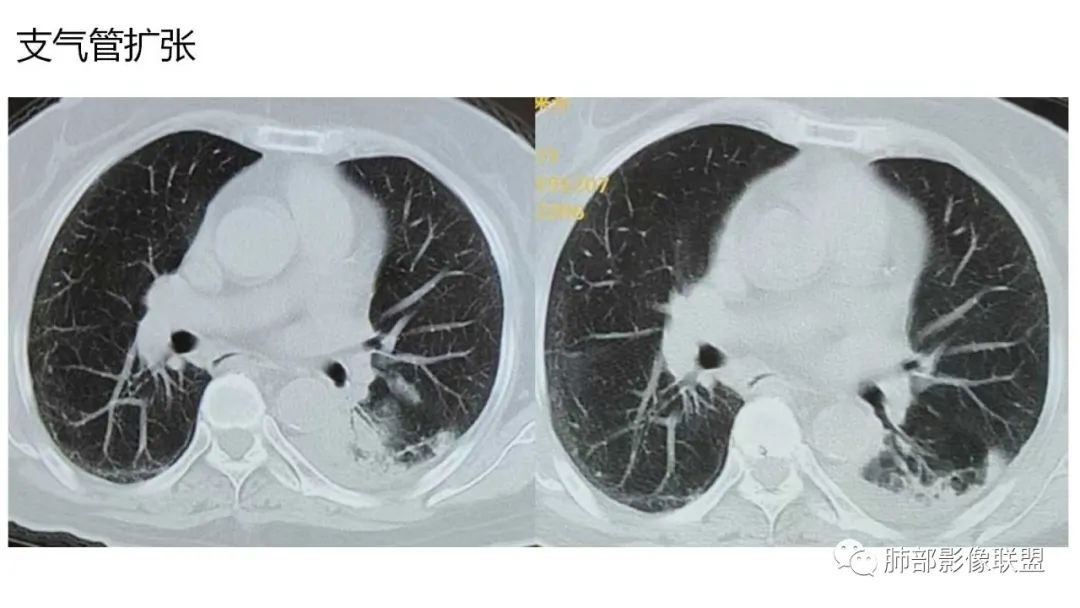

5、支气管粗细不均,呈“枯树枝征”,但与肺炎这一点鉴别不具有统计学差异。可发生支气管扩张